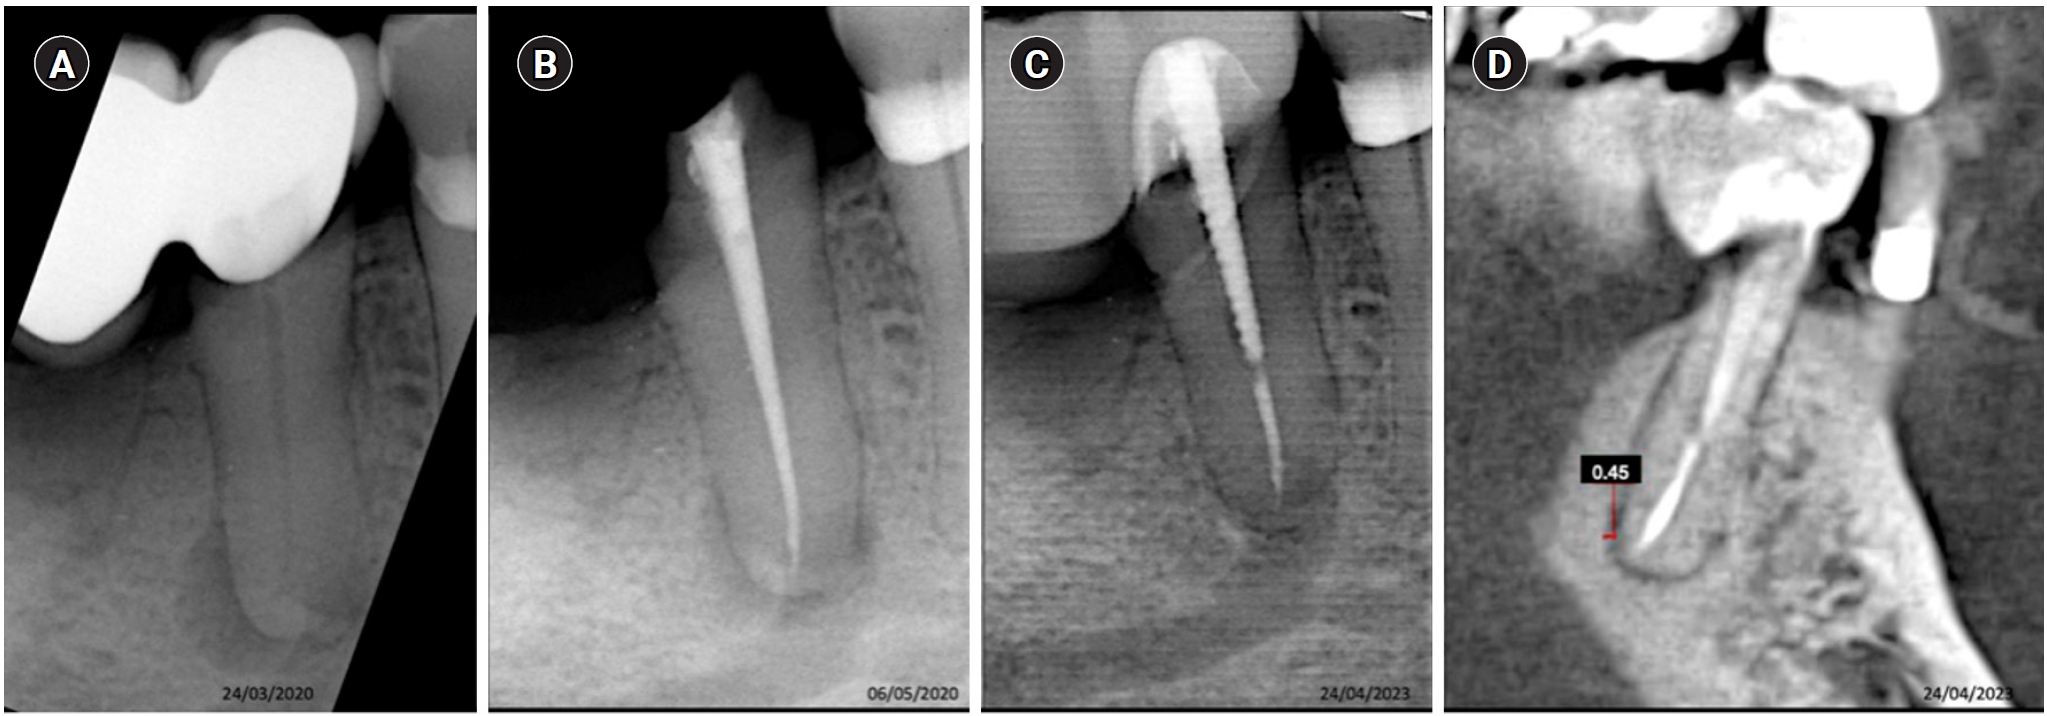

Tooth 16 with a diagnosis of previously initiated endodontic treatment and acute periapical abscess. (A) Diagnostic X-ray. (B) Immediate after obturation. (C) Tomographic control after 30 months, showing the apical lesion in the same manner as in the initial X-ray, considered a failure.

Tooth 36 with a diagnosis of previously treated with symptomatic apical periodontitis. (A) Diagnostic X-ray. (B) Immediate after obturation. (C) Tomographic control after 40 months, showing the apical lesion in the same manner as in the initial X-ray, considered a failure.